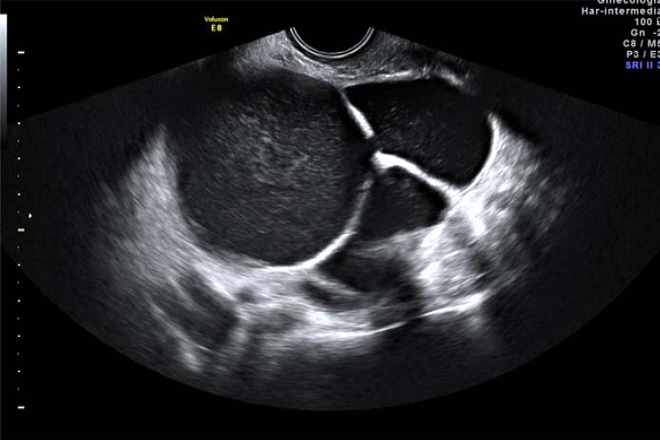

Abordaje diagnóstico por imagen en patología benigna de la vesícula y vías biliares

El ultrasonido es el método de imagen inicial recomendado para la evaluación de pacientes que se presentan con síndrome ictérico o con dolor en el cuadrante superior derecho debido a la capacidad del ultrasonido para evaluar órganos adyacentes y a su capacidad de localizar sitios